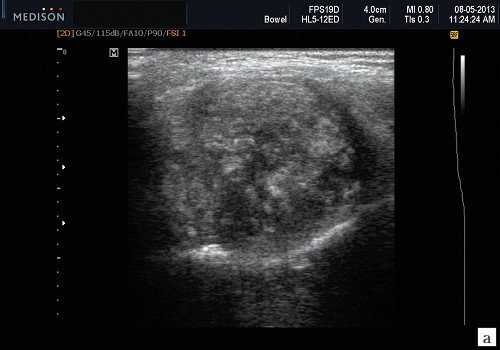

Морфология. Малая плеоморфная аденома: одиночная, цельная, яйцевидная и хорошо разграниченная опухоль. Большая плеоморфная аденома на УЗИ: дольки ± кровоизлияние или некроз ± кальцификация

Серошкальное УЗИ. Хорошо выраженная, солидная и гипоэхогенная по сравнению с прилегающей тканью слюны. Однородная внутренняя эхо-структура с задним акустическим усилением. Опухоль имеет несколько тканевых границ и позволяет звуку легко проникать, вызывая улучшение заднего отдела. Большие опухоли могут иметь неоднородные внутренние эхосигналы из-за кровоизлияния и некроза. Гетерогенная плеоморфная аденома может иметь нечеткие границы, имитирующие злокачественную опухоль. Большие опухоли могут иметь дольки и появляться на ножке. Необычный кальциноз при ультразвуковом сканировании наблюдается при давней опухоли. Кожа и подкожные ткани в норме

Плеоморфная (полиморфная) аденома (смешанная опухоль СЖ) - аденома СЖ, построенная из двух типов клеток: эпителия протоков и миоэпителиоцитов. Макроморфологическая картина. Опухоль обычно представляет собой эластичный или плотный узел дольчатой серовато-белой ткани, как правило, инкапсулированный частично. Типичной для плеоморфной аденомы является так называемая хондроидная строма, напоминающая гиалиновый хрящ. Варианты эхографического изображения плеоморфных аденом представлены на рисунке 8.